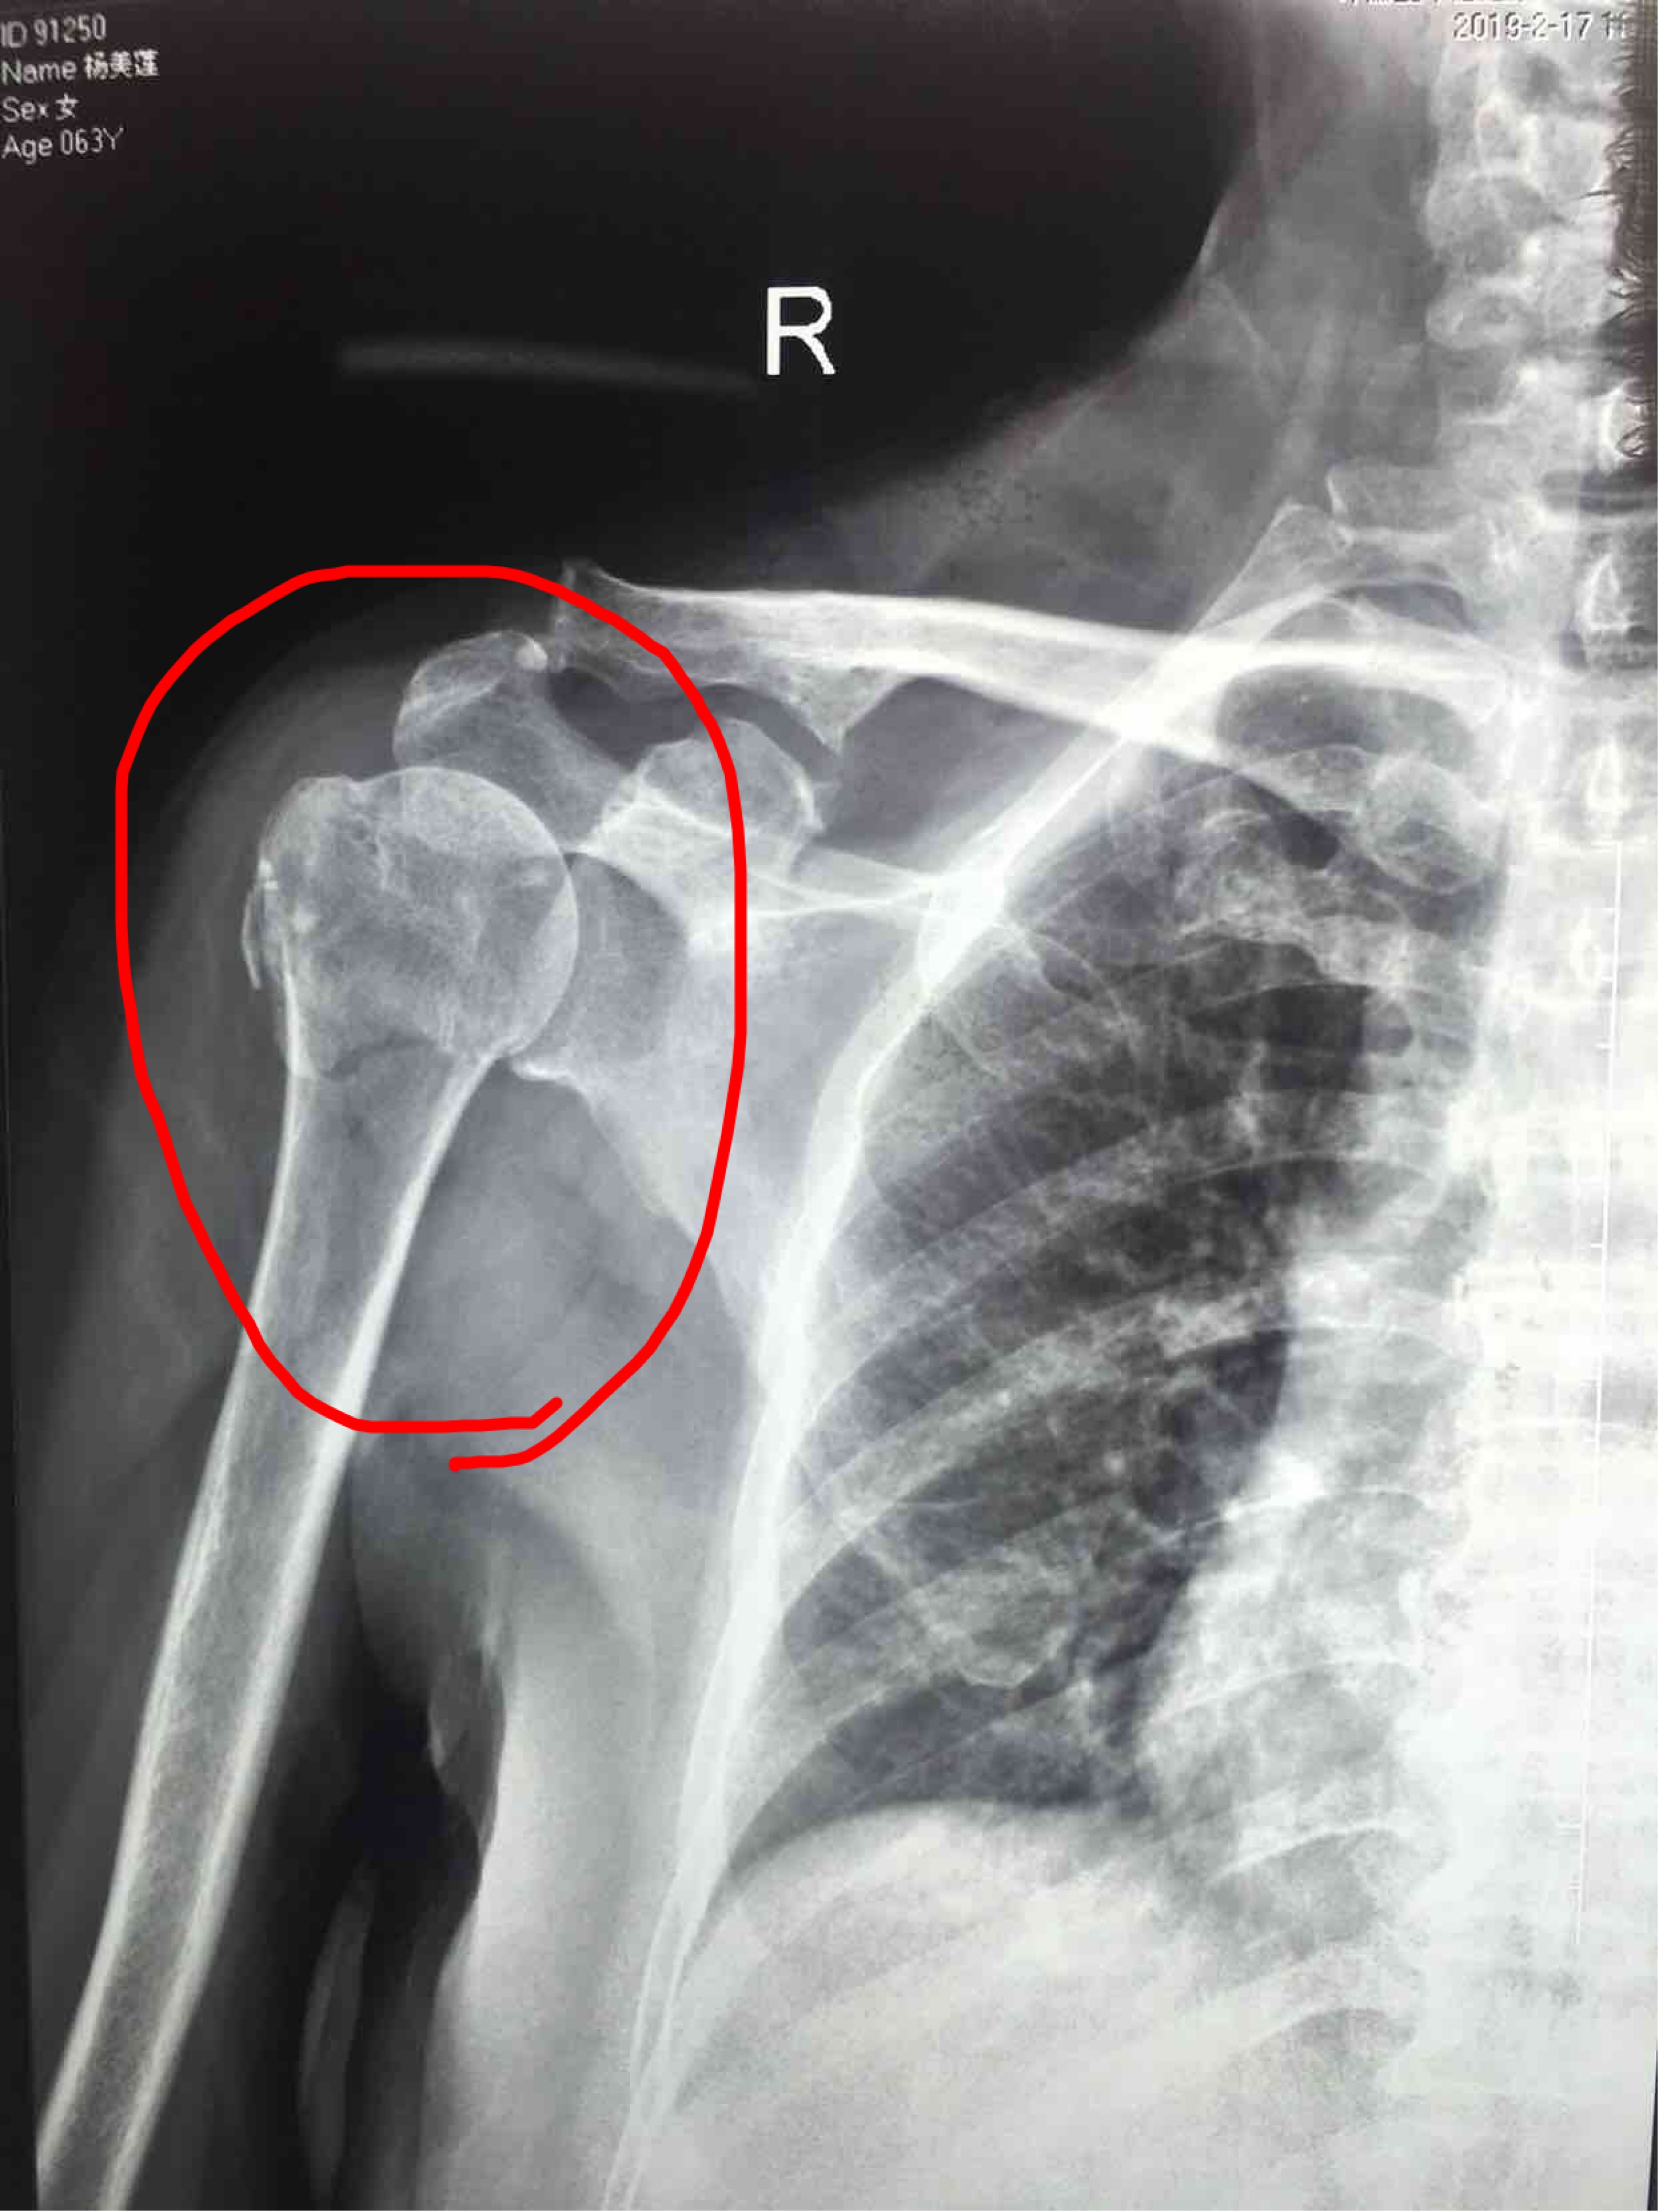

摔伤后右肩部肿痛活动受限1小时入院。既往患高血压5年左右,最高为160/90毫米汞柱。无特殊不良嗜好。

生命体征平稳,心肺腹未见异常。右肩部肿胀明显,局部皮色皮温基本正常,压痛及纵叩痛阳性,可及骨檫音及骨檫感,肩关节活动受限,末梢血运感觉正常。

诊断:肱骨外科颈粉碎性骨折(右)完善术前准备,在臂丛麻醉下行切复内固定术,选肱骨近端锁定钛板,保持稳定性及早期功能锻炼。术后抗炎,消肿等处理。